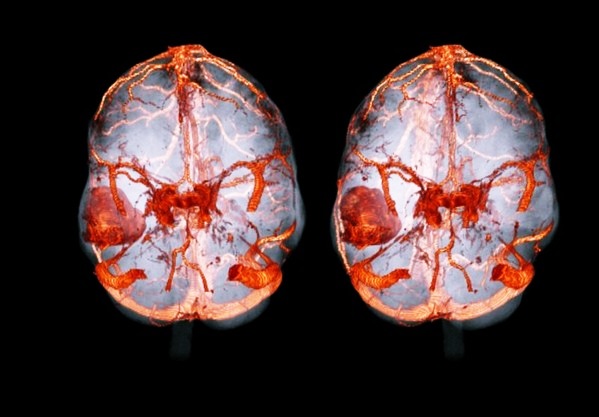

- методика очень информативна и помогает дать полную картину сосудистой системы даже без введения контрастного вещества;

- болезней и аномалий в сосудах головного мозга;

- аномалий в сосудах головного мозга. В данную категорию входит развитие аневризмов, тромбозов;

МРТ поможет определить расположение тромба, объем поражения головного мозга. Самое главное – МР-томография головного мозга позволяет отличить ишемический инсульт от геморрагического, что значительно влияет на тактику лечения и может спасти пациента от тяжелых последствий и гибели, энцефалит, менингит.

Основное отличие МРТ сосудов головного мозга и МРТ головного мозга заключается в том, что эти два обследования дают нам совершенно разный фокус сканирования, и назначаются они для выявления совершенно разных заболеваний головы.